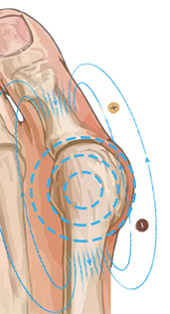

С целью устранения Hallus valgus (бурсита) и негативных симптомов, сопровождающих деформацию ступней, успешно применяется магнитотерапия. Магнитотерапия – уникальный метод физиотерапевтического лечения с помощью воздействия на организм постоянным, переменным или бегущим магнитным полем. Процедура является безопасной и не вызывает болезненных ощущений.

Чтобы купировать воспалительный процесс, достаточно использовать магнитную шину MAGNETFIX ежедневно в течение 3-5 часов. Это способствует не только выравниванию фаланг пальцев и уменьшению деформации, но также благодаря воздействию магнитов происходит стимуляция нервных окончаний, повышается тонус тканей, улучшается кровообращение. MAGNETFIX фиксирует большой палец в нужном положении, снижает нагрузку на ступни, купирует боль, облегчает ходьбу и возвращает здоровья ступням.